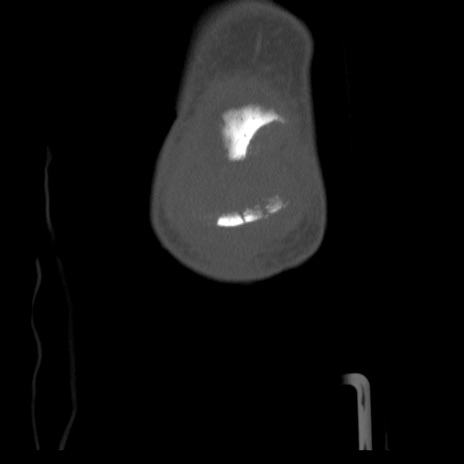

右膝関節CT

横断像